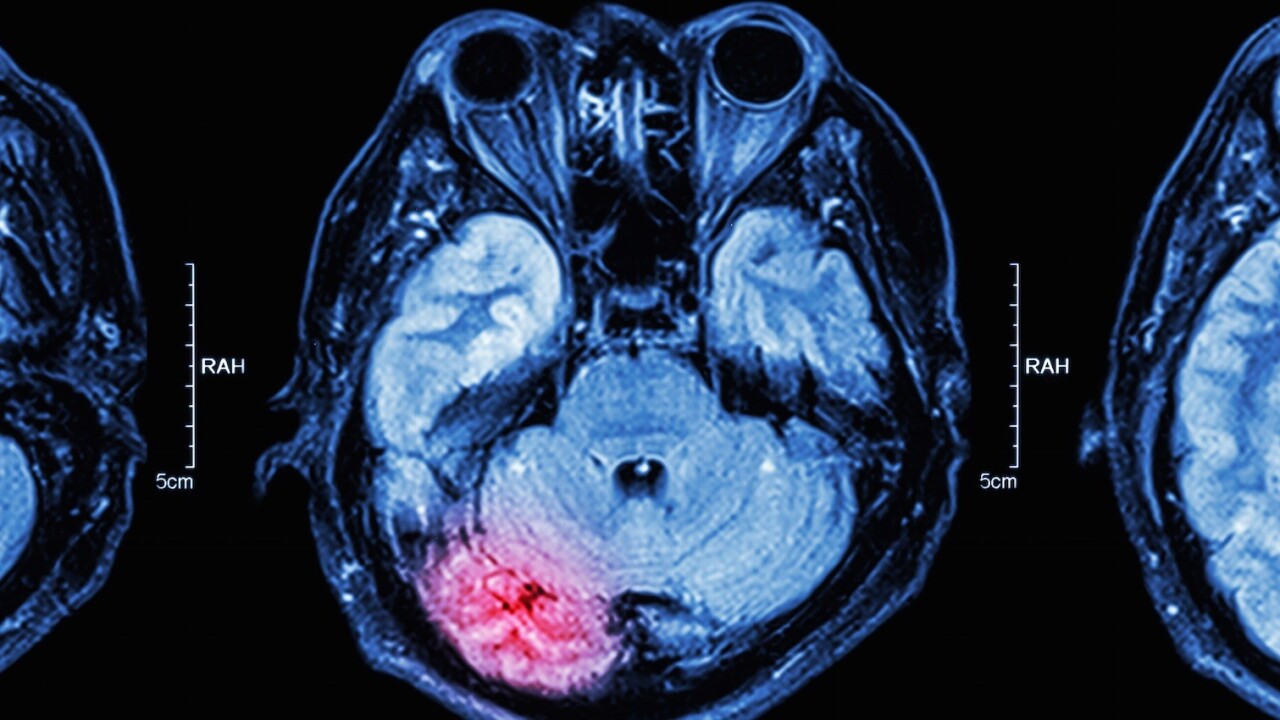

In a 2013 study conducted by psychologists at UCLA, the researchers were, for the first time, able to determine which brain regions are associated with ideas that become contagious and which regions are associated with being an effective communicator of ideas.

The TPJ or the temporoparietal junction is this area of the brain that lit up during functional magnetic resonance imagine (fMRI) brain scans when people were first exposed to new ideas that they would later recommend.

Matthew Lieberman, a UCLA professor of psychology and of psychiatry and biobehavioral sciences and author of the book Social: Why Our Brains are Wired to Connect, noted:

Our study suggests that people are regularly attuned to how the things they’re seeing will be useful and interesting, not just to themselves, but also to other people. We always seem to be on the lookout for who else will find this helpful, amusing or interesting, and our brain data are showing evidence of that. At the first encounter with information, people are already using the brain network involved in thinking about how this can be interesting to other people. We’re wired to want to share information with other people. I think that is a profound statement about the social nature of our minds.